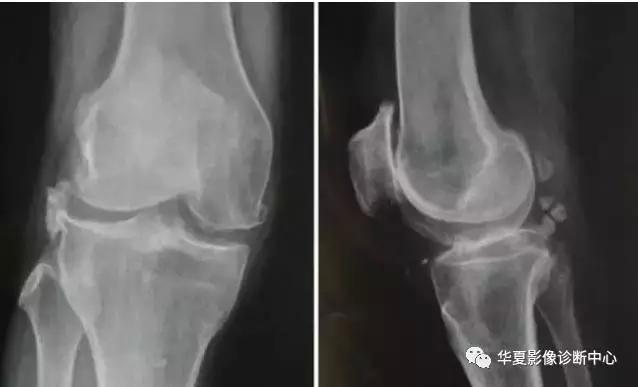

16骨关节炎

常见(>50岁)

膝关节痛

早期:活动开始时痛、剧院征、上下楼梯时痛、下蹲起立时痛,休息能缓解;

中后期:负重痛、行走痛、夜间痛

短时晨僵 (<20分钟),活动后消失

可有滑膜炎急性发作,关节间隙压痛,活动度减少

关节摩擦音,轻~中度关节积液

X线摄片:负重位前后位、侧位和髌股关节切线位。